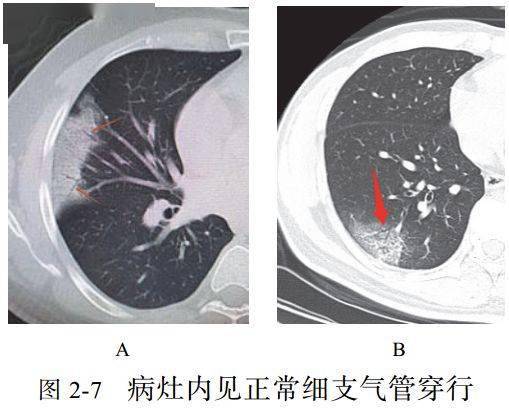

(七)空气支气管征

实变肺组织内可见含气支气管正常穿行,未见明显狭窄和扭曲,少部分病例可以看到支气管壁增厚,管腔通畅

而晚期病变可以出现支气管牵拉、扭曲征象(图 2-7)